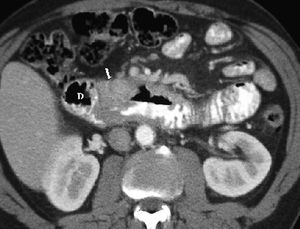

La lesión duodenal por traumatismo es rara y es la tercera porción del duodeno la que con más frecuencia se lesiona al ser comprimida contra la columna. Se puede producir contusión o perforación, observándose en ambas situaciones engrosamiento de la pared duodenal, borrosidad de la grasa periduodenal o líquido en el espacio pararrenal anterior derecho. En caso de contusión se puede identificar el hematoma como una colección de densidad intermedia o alta que comprime la luz duodenal en la TC. Signos de perforación son la presencia de aire adyacente al duodeno retroperitoneal (fig. 3) o la extravasación de contraste oral al retroperitoneo9,10.

Fig. 3--Perforación duodenal traumática. Estudio de tomografía computarizada que muestra aire en retroperitoneo (flecha) tras traumatismo.